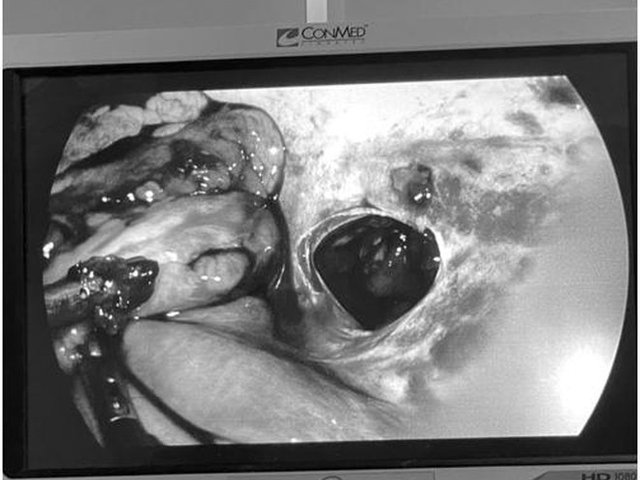

Chị P.T.L, sinh năm 1986, ở quận Long Biên (Hà Nội) được đưa vào Bệnh viện Đa khoa Đức Giang cấp cứu với vết thương...